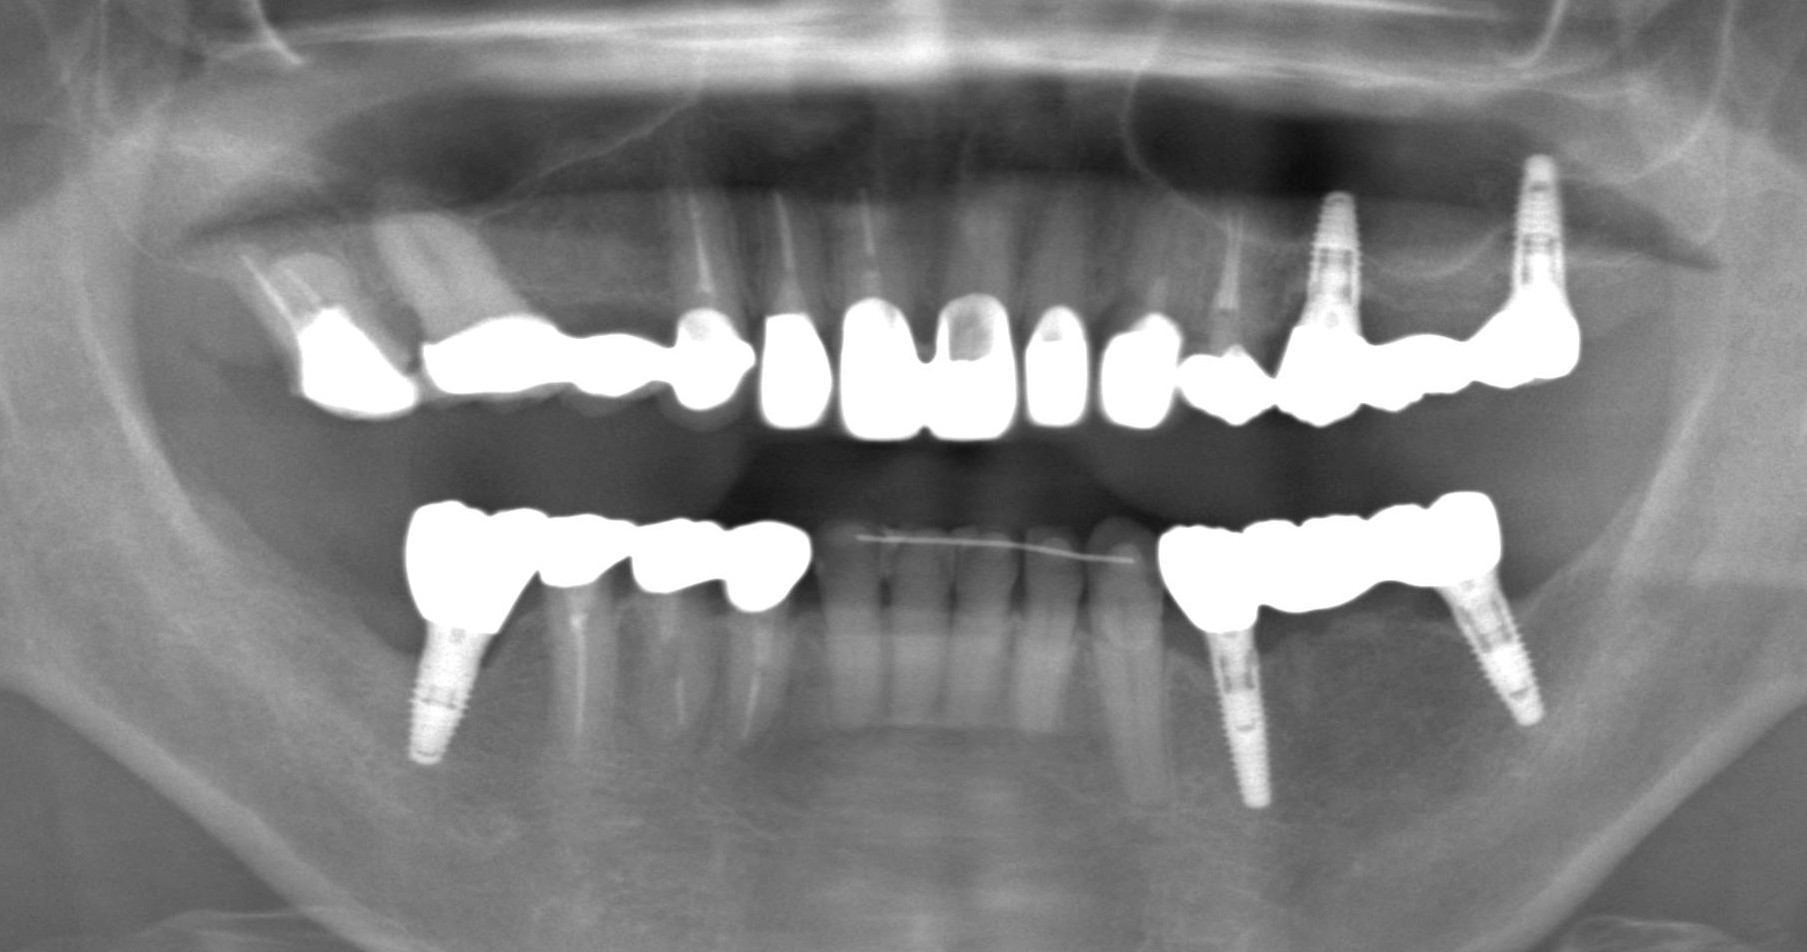

症例11

50代 男性 なんでも食べられるようになりたい

術前咬合面

術前咬合面

術後咬合面

術後咬合面

| 主訴 | 自分が一番元気に、何でも食べられる父親でいたい。家族との食事の時間が人生ですごく大切で、何とかしたい、と思っていた。 |

|---|---|

| 年代・性別 | 50代 男性 |

| 治療部位 | 上顎6~6 |

| 治療費用 |

インプラント手術料 |

| 手術回数 | 1回 |

| 治療期間 | 4ヶ月 |

| 手術時間 | 180分 |

| 治療回数 | 10回 |